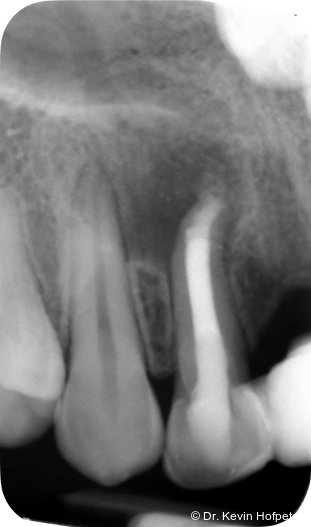

Klinisch zeigten sich die Zähne 12 und 13 karies- und füllungsfrei. Zahn 12 reagierte nicht auf Sensibilitätstests und war leicht perkussionsempfindlich. Zahn 13 reagierte unauffällig. Radiologisch zeigte sich eine ausgedehnte apikale Aufhellung am Zahn 12 sowie eine Hartgewebsformation im apikalen Kanallumen (Abb. 1–2d).

Geplant wurde eine Wurzelkanalbehandlung an Zahn 12. Die zunächst vorgesehene Zystektomie mit Wurzelspitzenresektion wurde zurückgestellt, um die Heilungstendenz nach orthograder Therapie zu beurteilen und einen chirurgischen Eingriff möglichst zu vermeiden.